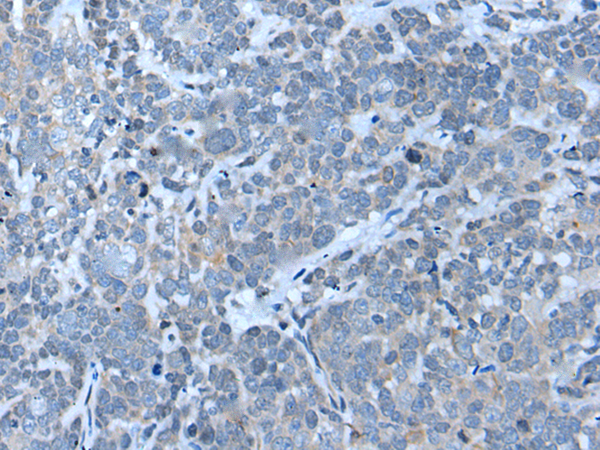

ELISA, IHC

IHC positive control:

Human ovarian cancer and human thyroid cancer

IHC Recommend dilution:

20-100